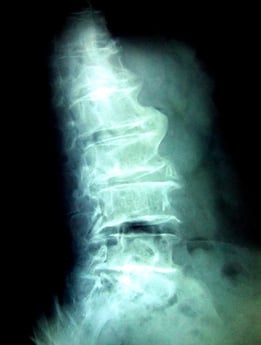

脊柱管狭窄症

3年前から腰痛、左足の痺れがありMRI検査で脊柱管狭窄症と診断される。

視診 腰椎後弯、腰仙角の亢進、